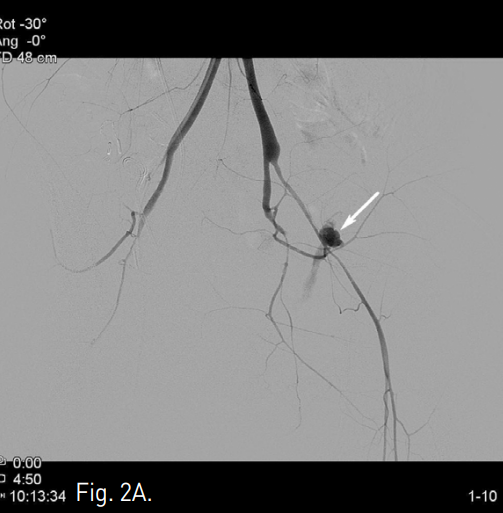

C. Left iliac angiogram obtained immediately after stent graft placement shows no evidence of active extravasation or pseudoaneurysm at the left external iliac artery.